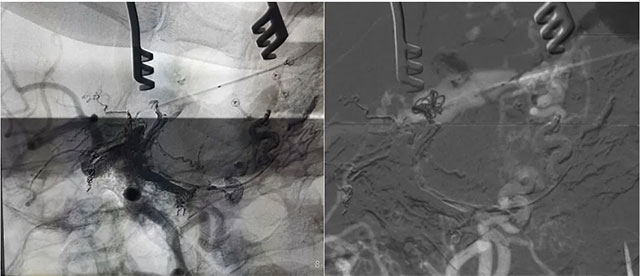

▲ 再次造影確認(rèn)位置后,填入 HELIX 6/20彈簧圈

▲ 微導(dǎo)管造影確認(rèn)后,注入 Onyx 18膠 5ml

經(jīng)左側(cè)股動(dòng)脈以單彎造影管超選至左側(cè)頸總動(dòng)脈造影明確靜脈穿刺點(diǎn)入路,予以穿刺針穿刺成功后造影明確在位,隨后 Echelon 10微導(dǎo)管到位橫竇,填入一枚彈簧圈做塞子,造影明確位置后,緩慢注入 Onxy18膠 5毫升,鑄膠彌散良好,通過靜脈逆向彌散至部分供血?jiǎng)用}內(nèi)。復(fù)查造影,見瘺口完全被栓塞,引流靜脈消失,手術(shù)成功。